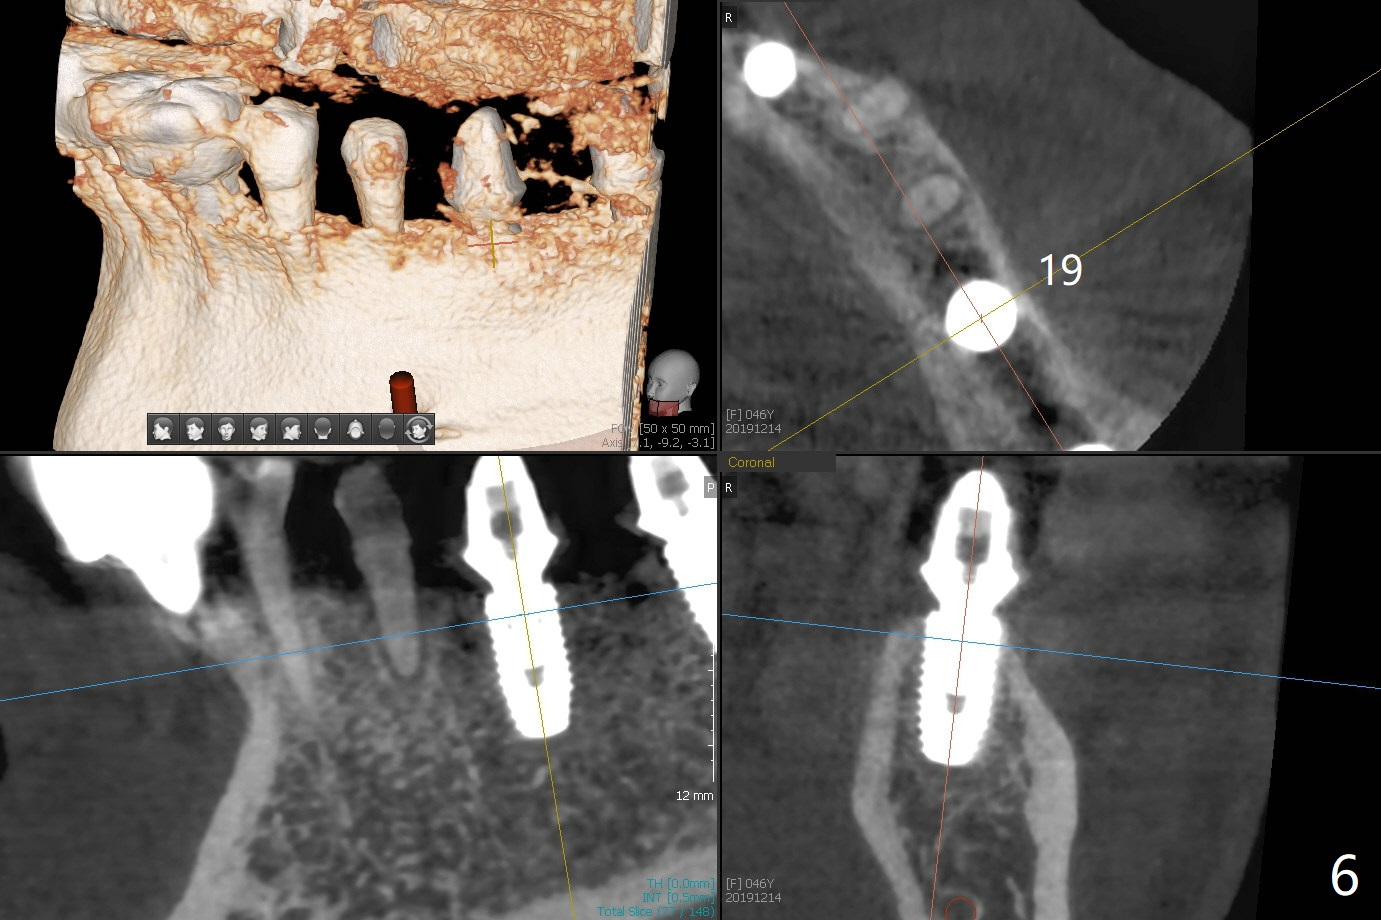

Re-analysis of preop CT reveals extensive bone loss around #18 (Fig.1 (lingual view)). Blood is withdrawn for sticky bone. After implant placement (Fig.2), sticky bone is placed at #18 (Fig.3 red dashed line (yellow: superior border of the Inferior Alveolar Canal)). PRF membrane and an immediate provisional FPD (#18-20) further keep the bone graft in place for healing. Four months postop, the patient reports difficulty in mastication on the left and requests extraction of the tooth #20 for implant (Fig.4). The implant will be placed lingually, while socket shield will be performed buccally (Fig.5 S) to keep bone graft in place. The implant at #19 is equicrestal (Fig.6); the one at #18 is apparently supracrestal buccally (Fig.7). Since there is a lot of scattering from nearby crowns, the implant at #20 will be placed free hand. To overcome the thick dense lingual plate (Fig.8 L), osteotomy is initiated (Fig.9 red line) in the middle of the lingual wall of the extraction socket (black area) on the top of the socket shield (S). After the last drill (3.5x11.5 mm, Fig.10 pink) and before 4x11.5 mm implant, use Lindamann bur to remove the coronal portion of the lingual plate (Fig.11 red line) to prevent implant buccal deviation.